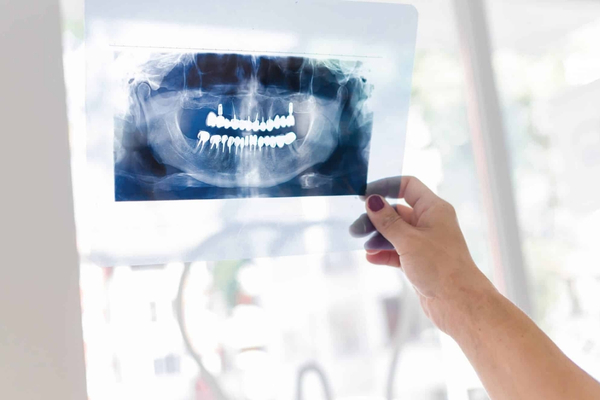

Radiografia

Panorâmica

A Panorâmica é uma radiografia extraoral que fornece uma imagem bidimensional de toda a boca em uma única tomada. Ela permite uma visão geral das arcadas dentárias, maxila, mandíbula, seios da face e articulações temporomandibulares (ATM). É um exame de triagem fundamental para a avaliação inicial, detecção de cáries extensas, cistos, tumores, avaliação de dentes do siso e análise do suporte ósseo, sendo a base de muitos diagnósticos na odontologia.